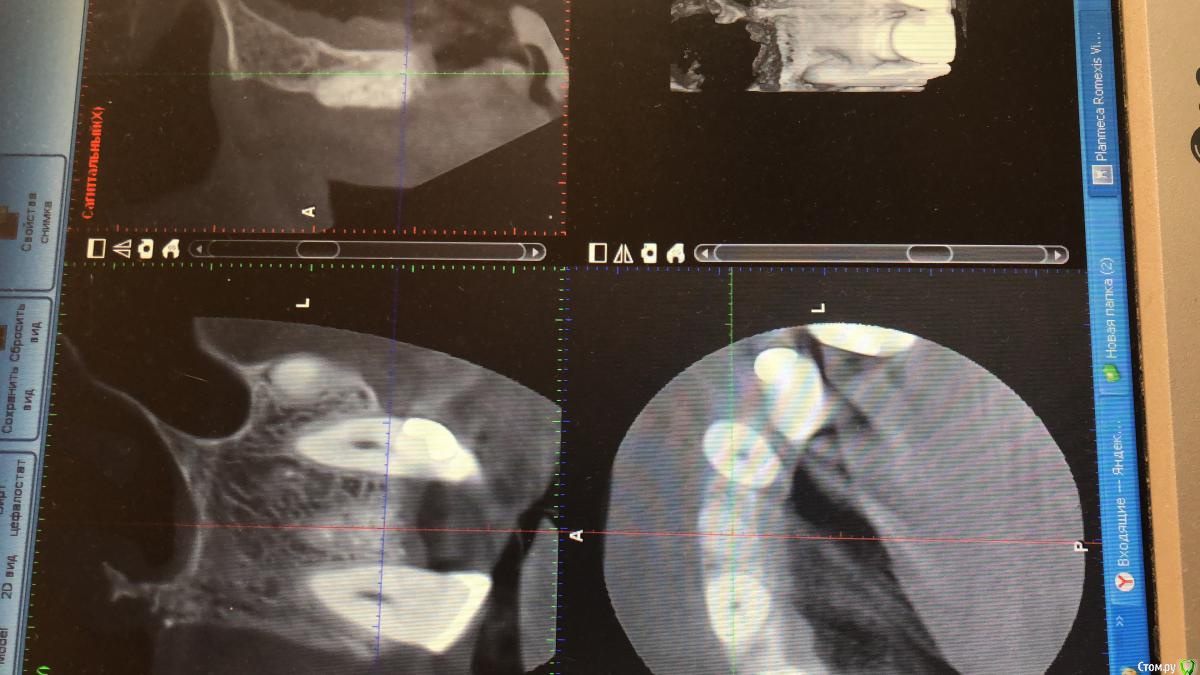

Ординатор Опубликовано 18 сентября, 2018 Поделиться Опубликовано 18 сентября, 2018 3 месяца назад удалил зуб, для одномоментной кости было мало. Подсыпался biooss сегодня сделала кт. Сколько бы вы ещё выждали? Ссылка на комментарий

Дмитрий Л. Опубликовано 20 сентября, 2018 Поделиться Опубликовано 20 сентября, 2018 3 месяца назад удалил зуб, для одномоментной кости было мало. Подсыпался biooss сегодня сделала кт. Сколько бы вы ещё выждали?Ещё полгода. Ссылка на комментарий